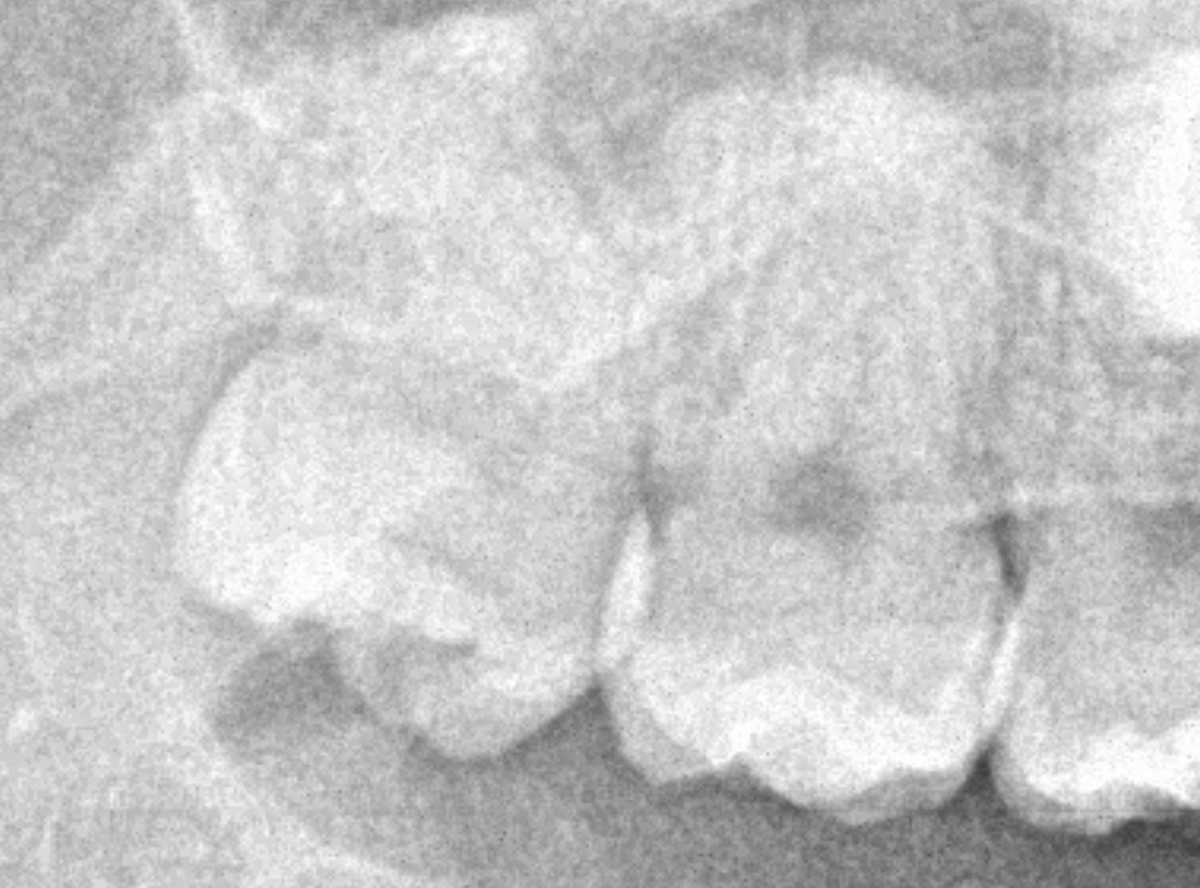

ここでは、比較的簡単なおやしらずの抜歯の例を中心にご紹介します。

このようなおやしらず、あなたはありませんか?